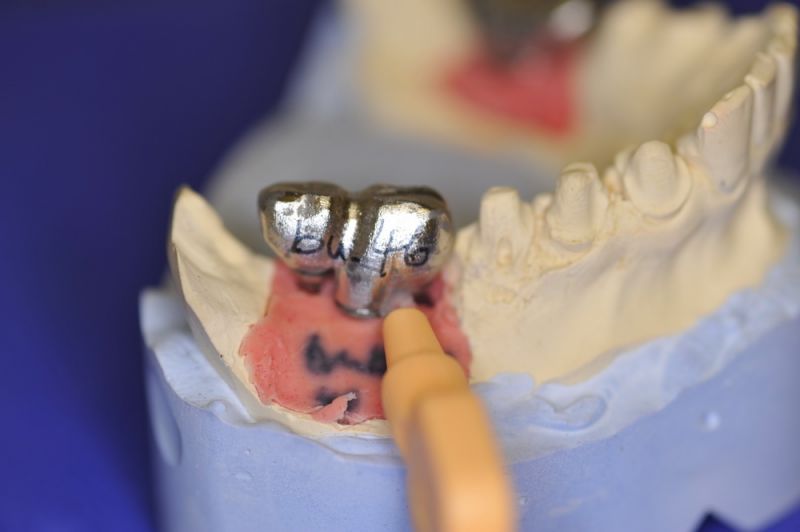

Nun stellte sich heraus, dass der Abstand zwischen den Implantaten sehr gering war, weil die Einschubrichtungen der Aufbauten sich zum Teil gegenseitig im Wege standen. Konfektionierte Teile mussten individuell umgeschliffen werden, dabei das Ziel, den Biss korrekt einzustellen nicht aus dem Auge zu verlieren.

Heute war nun Gerüsteinprobe, mit all den Problemen der Umsetzung zwischen Laborsituation und Mundsituation. Siehe Stichpunkt "Schnittstellenproblematik"! was bei Zähnen, auf Grund deren Eigenbeweglichkeit im Kieferkochen kein Problem wäre, ist bei drei unbeweglichen Implantaten ein Riesenproblem. Darüber spricht nur in aller Regel Niemand! Es musste viel fein nachgearbeitet werden.

4 Stunden haben wir heute Temporäre Aufbauten und provisorische Kronen entfernt. Definitive Aufbauten im Munde eingeschraubt. Eine erneute Bissregistrierung durchgeführt und die Arbeit neu artikuliert. Neue Provisorien mussten auch wieder hergestellt werden.